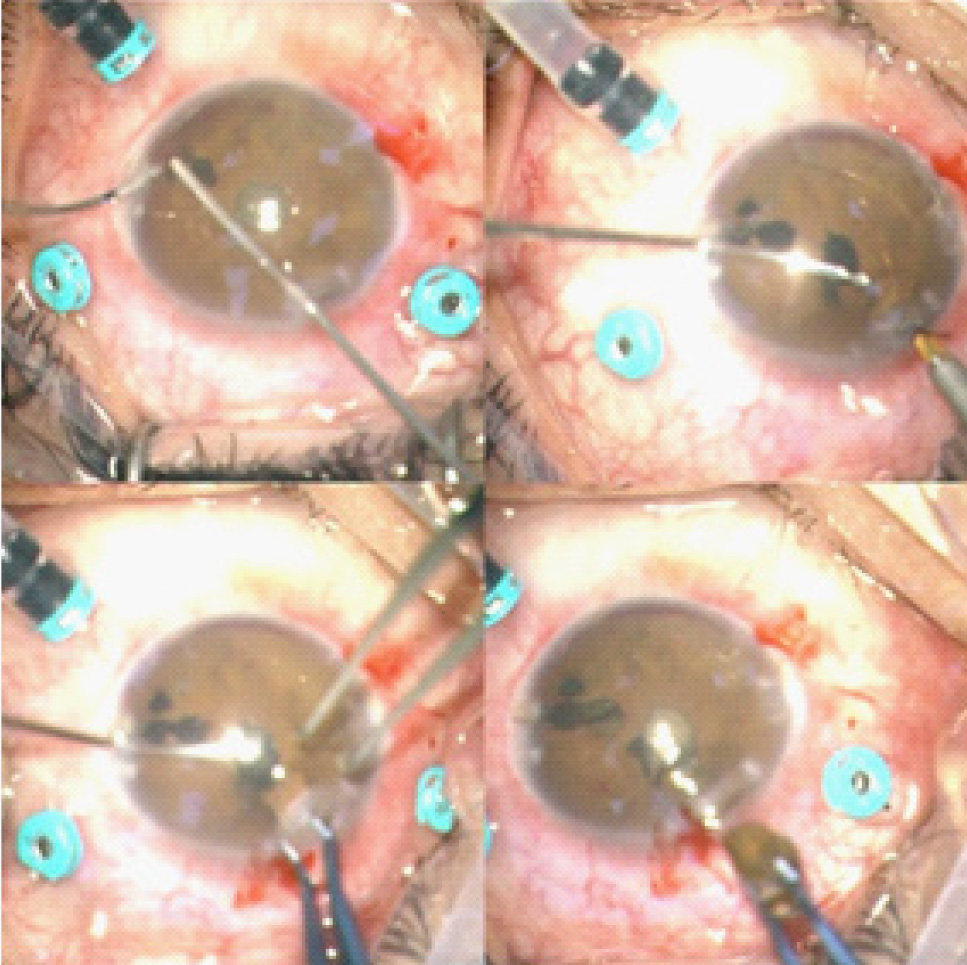

Во время операции взято содержимое передней камеры для посева, камера заполнена вискоэластиком. С помощью витреотома выполнена колобома по меридиану 4 часа в проекции инородного тела, инородное тело извлечено при помощи внутриглазного магнита и корнеосклерального пинцета (рис. 6). Установлены ирис-ретракторы. Установлены 25G порты, взято содержимое для посева из витреальной полости. На средней периферии сетчатки в нижней половине визуализировались витреоретинальные тракции, в макулярной области – хрусталик черного цвета. После витрэктомии и тампонады витреальной полости ПФОС хрусталик был выведен в переднюю камеру и удален с помощью хрусталиковой петли через разрез роговицы, далее разрез ушит швом по Пирсу (рис. 7). В макулярной зоне после удаления хрусталика обнаружен старый обширный макулярный разрыв. В витреальную полость и в переднюю камеру введен раствор антибиотика. По результатам бактериологического исследования в посевах из передней камеры и витреальной полости были обнаружены Acinetobacter baumani (101 КОЕ/тампон), Klebsiella pneumoniae (101 КОЕ/тампон), Escherichia coli (101 КОЕ/тампон).

Рис. 6. Извлечение ВГИТ

Рис. 7. Введение ПФОС; извлечение хрусталика; фото извлеченных хрусталика и ВГИТ